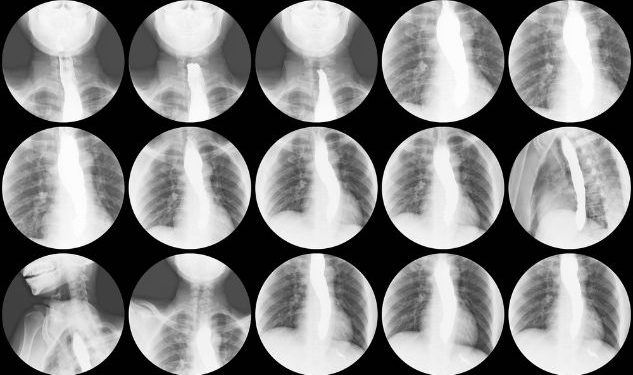

If you have esophagogastric varices, your doctor may recommend an endoscopy to see the inside of your upper digestive tract. An endoscope is a thin, flexible tube with a camera on the end that is inserted through your mouth and guided down to the esophagus and stomach. The camera sends images to a monitor, which the physician can use to detect enlarged veins that might be causing bleeding.

Other tests to diagnose esophagogastric varices are X-rays and CT scans. These tests provide pictures of the liver or blood flow in the liver and allow the provider to identify enlarged veins that might be causing esophagogastric varices and a risk for bleeding.